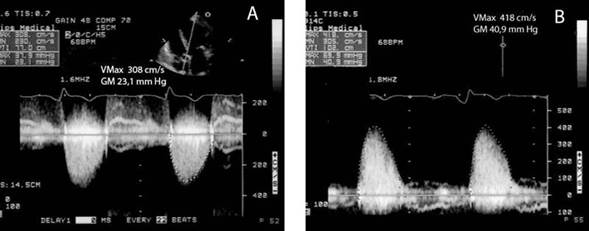

Cuando se catalogó la EA solamente por ÁPEX (Tabla 4), 56 fueron clasificadas como severas y 44 como no severas (33 como moderadas y 11 como leves). La utilización del enfoque PED reclasificó como severas 18/33 (54,6%, IC 95% 36,4-71,9) que eran moderadas por ÁPEX (Figura 1) y 3/11 (27,3% IC 95% 6,0-61,0) leves por ÁPEX (Figura 2) . En total 21/44 (47,7%) de las EA no severas por ÁPEX fueron reclasificadas como severas por PED, es decir uno de cada dos pacientes.

Figura 2 Registros desde ÁPEX y PED en el mismo paciente. A: ÁPEX con valores de VMáx y GM que catalogan la EA como leve. B: PED con Pedof con VMáx y GM correspondientes a EA severa.